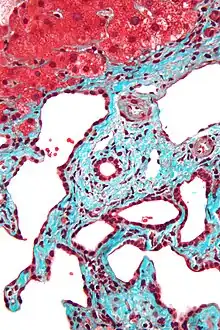

Histopathology of a bile duct hamartoma, high magnification, H&E stain. It shows typical features of bile duct hamartoma:

Micrograph of a bile duct hamartoma. Trichrome stain. Intermediate magnification

Micrograph of a bile duct hamartoma. Trichrome stain, high magnification